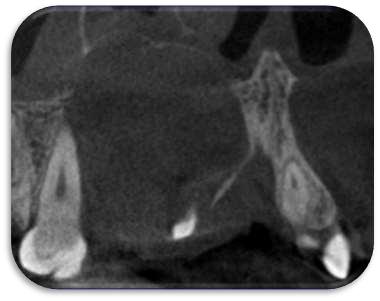

En el corte tomográfico oblicuo–sagital derecho se observa: (figura 3)

Imagen hipodensa, bien delimitada, de contorno redondeado, ubicada en el seno maxilar derecho.

La lesión parece originarse desde el piso del seno, con íntima relación con los ápices dentarios superiores posteriores.

No se aprecian signos de erosión ósea marcada, aunque existe adelgazamiento del piso sinusal

La densidad es homogénea, lo que orienta hacia un contenido quístico

Conclusión

Seno maxilar derecho: ocupándolo parcialmente, se identifica una imagen hipodensa, bien delimitada, de contorno redondeado y homogéneo, compatible con lesión quística

Produce expansión con adelgazamiento de la pared ósea sin clara evidencia de destrucción.